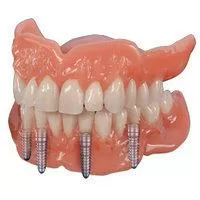

- Протезирование зубов на имплантах

Виды протезирования, имплантации при полном отсутствии зубов

Все зубы без костной пластики — сэкономим время и деньги